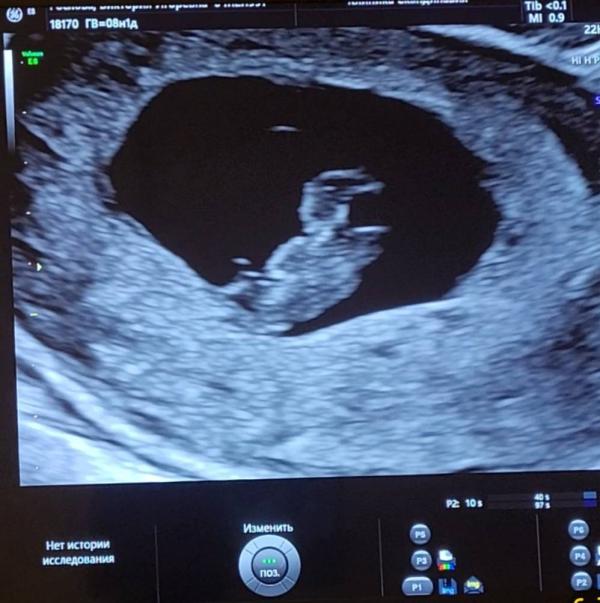

Меня так всё-таки удивляет женский организм. Не верится, что из точки в посте ниже 2 недели назад уже вырос почти целый человек, с которым мы сходили на свидание сегодня.

Держись крошечка 🤎тебя очень ждут!